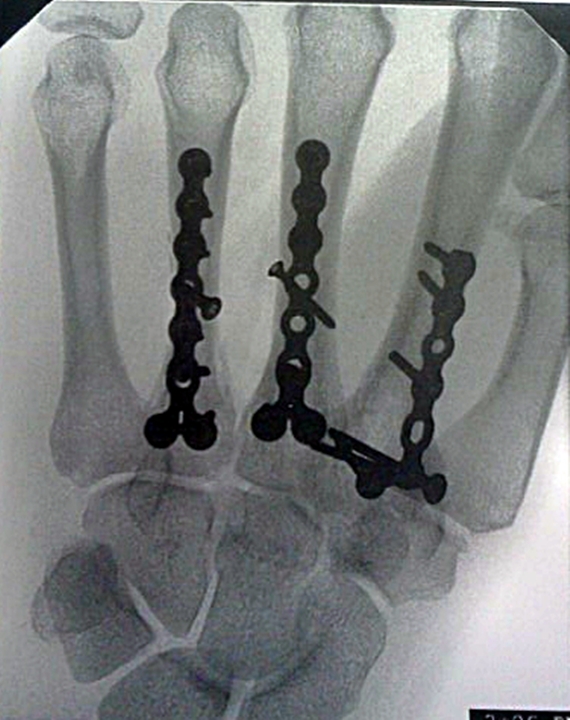

It's been one year since my little mishap. Although my hand will never be quite the same

--obviously with this crazy hardware of 20 screws and 4 plates--I have recovered well--and can still crochet!! And the scars are barely noticeable--in good light. Every time I ponder the healing that is required in this life, I can't help but be reminded of the healing power of the Savior. (There's a little post about it here.)